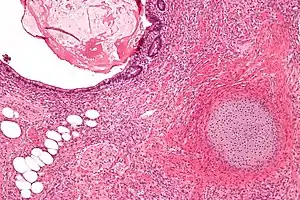

O cisto dermóide é um dos tumores mais comuns do ovário e um exemplo de teratoma. Macroscopicamente é um tumor cístico preenchido por cabelos e material sebáceo. A parede interna do cisto tem aspecto de pele, com epiderme, folículos pilosos, glândulas sebáceas e sudoríparas. Geralmente, em uma área da parede mais saliente na luz do cisto e chamada promontório, encontramos vários outros tipos de tecido, que tipicamente derivam dos três folhetos embrionários. Alguns cistos dermóides parecem um atlas de histologia normal pela variedade de aspectos. Porém, os tecidos estão topograficamente desorganizados e agrupados sem nenhuma 'lógica'. Em diversas áreas podemos reconhecer estruturas organóides, como a que lembra víscera oca, com musculatura lisa em duas camadas e portanto ate esboço de inervação autonômica. Vemos tecido nervoso central (ectoderme) com áreas de gliose e até diferenciação para córtex cerebelar. Há vários tipos de epitélio de revestimento: escamoso, cilíndrico ciliado, com ou sem células caliciformes, e do tipo intestinal (endoderme). Há ainda glândulas mucosas, serosas e sero-mucosas (também da endoderme) e tecidos de linhagem conjuntiva como músculo liso e osso (mesoderme). Em suma, qualquer tecido normal pode estar presente.

O cisto dermóide é benigno e todos os tecidos que participam são bem diferenciados. É mais comum durante a idade reprodutiva da mulher. Uma das teorias admite origem a partir de uma célula pluripotente, tipicamente de origem germinativa. Podem atingir grandes volumes (até alguns quilos) pela acumulação de material sebáceo no interior do cisto. As principais complicações são torção do pedículo vascular com infarto hemorrágico, ou ruptura do cisto na cavidade peritonial, provocando peritonite química.